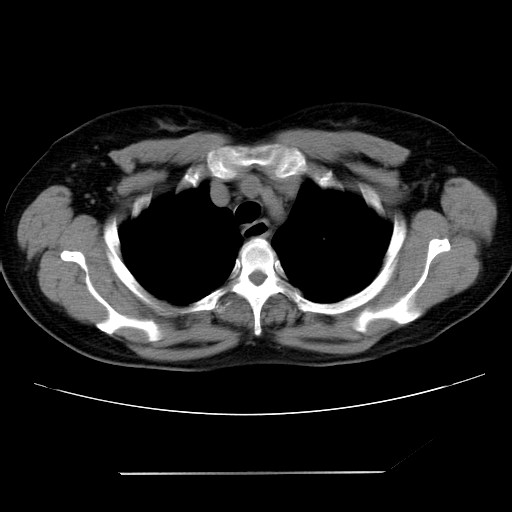

女性,62岁,长期咳嗽,既往从事工作有粉尘接触,有高血压病史,110/150mmhg,近日咳嗽加重,脸面浮肿,请大家帮看下,

1、尘肺;2、慢性支气管炎合并肺部感染;3、心影增大(左房、左室大),考虑高血压性心脏病。

慢支并肺部炎症;右肺结核球?主肺动脉、右肺动脉影不宽,右心室不大,不支持肺心病;无心包积液。